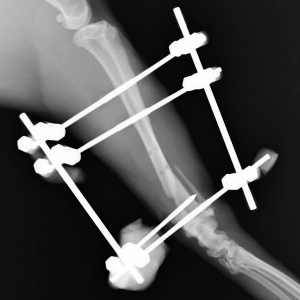

下は手術後の側面からのレントゲン写真です。しっかり固定できましたので、この後は骨の癒合を待つだけです。運動制限はありますが、創外固定の器具が健康な骨の代役を担ってくれますから、猫ちゃんは手術後には自由に動き回ることができます。

下の写真が手術後3か月目のものです。補強のためのレジンとピンの約半数を除去した後の写真です。